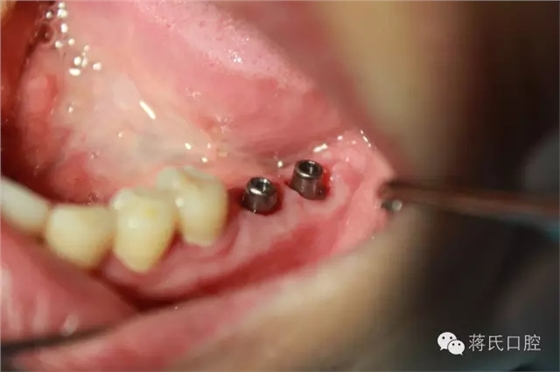

3.修復(fù)基臺以成品為主,優(yōu)點強度大,螺絲扣密和

4.修復(fù)后正面,咬合距離低以純鈦冠修復(fù),植體角度良好所以連冠修復(fù)